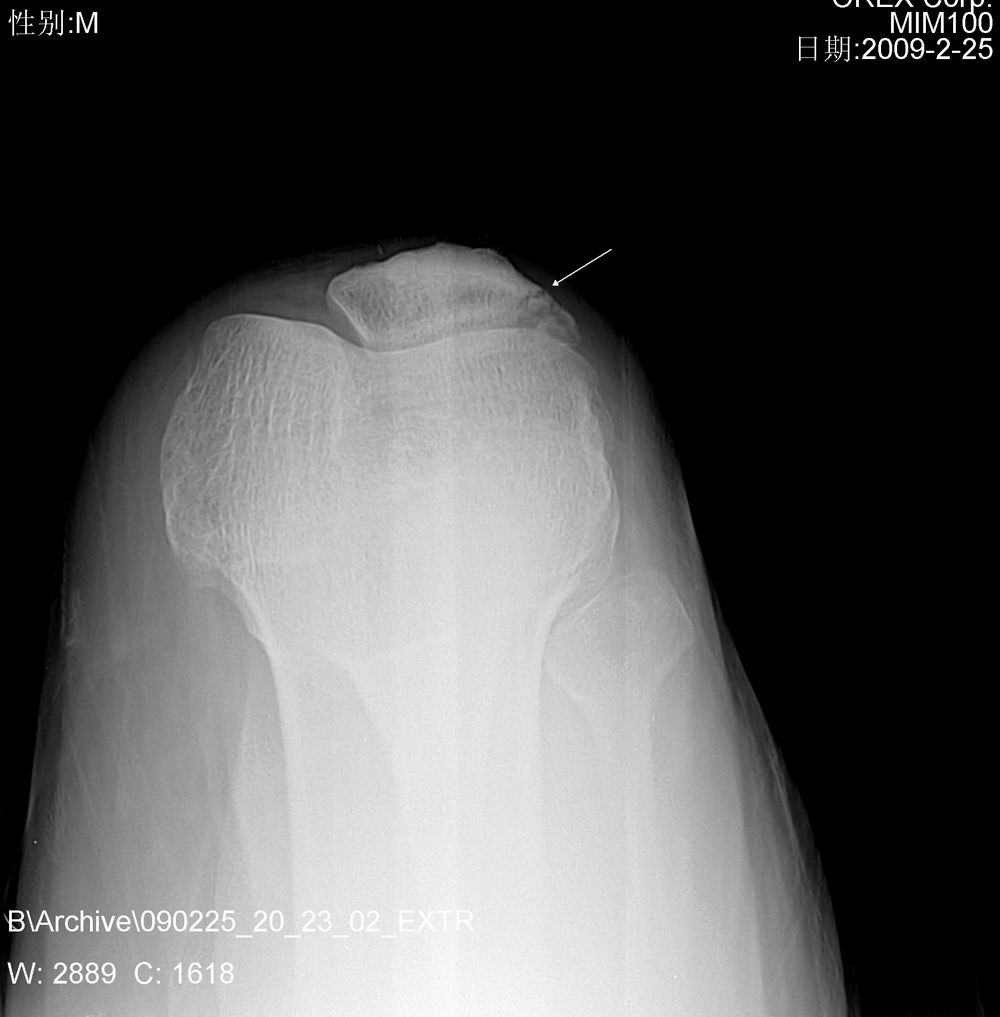

髌骨近外侧缘骨折。

——轴位投照值得俺学习。

好漂亮的轴位片,学习了

髌骨骨折。

轴位片很好。

髌骨外侧缘骨折,照得不错,如无轴位可造成误诊。

髌骨外侧缘骨折,轴位投照值得学习,谢谢

髌骨近外侧缘骨折。支持 轴位片拍的不错。

髌骨外侧缘撕裂性骨折。病人不配合还照得这么好。佩服。